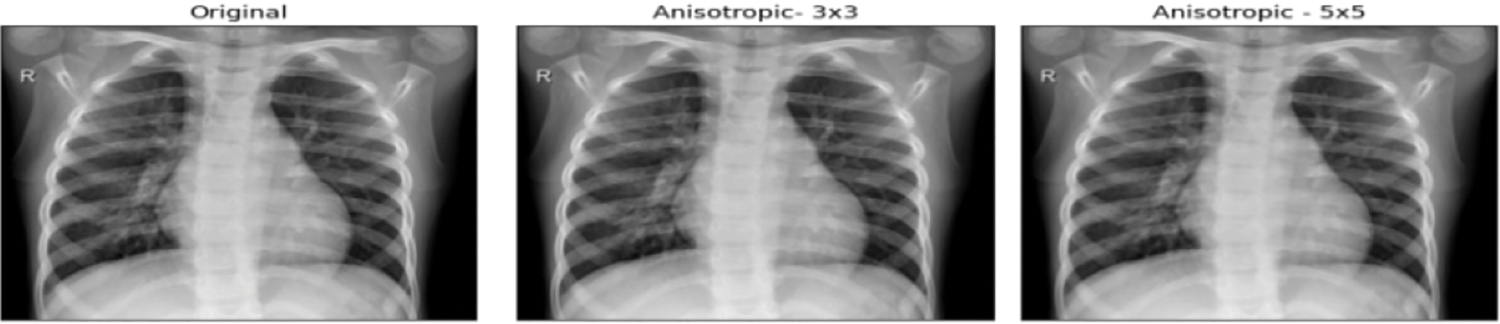

Around 234 normal, 390 Pneumonia, and 267 COVID-19 X-ray images are considered as input. Fig. 6 contains the images of various categories. The preprocessing results of the MADF technique are demonstrated in Fig. 7.

Figure 7: Preprocessed images